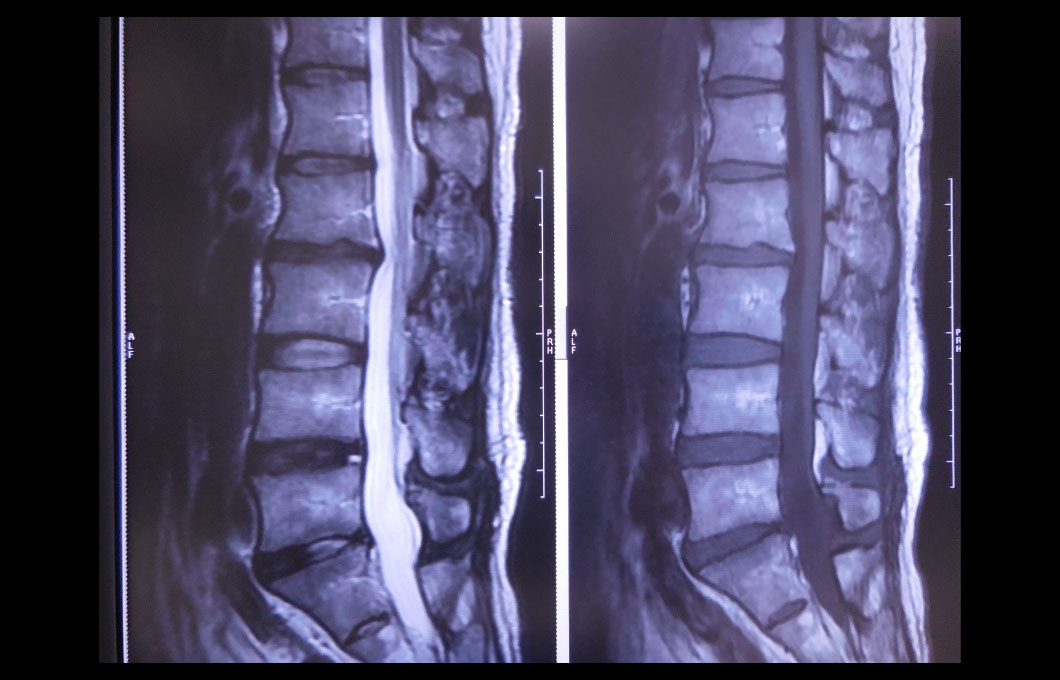

磁気共鳴画像といい、患者さまにトンネル内にある大きな磁石の中に入っていただき、磁気を利用してさまざまな断層像を写し出すことにより、より細やかな診断ができます。この検査の特徴は、X線を使用しないため放射線による被ばくがないことです。